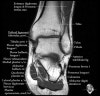

- Axial section

Axial PD fat suppression evaluates the tendons and ligaments of the ankle particularly after acute/subacute injuries. It also is sensitive to talar dome osteochondral defects. Alternatively, a T2 sequence can be used to eliminate magic angle artifact that may occur as the tendons travel around the malleolar turns.

Tibiofibular ligaments

Lateral ankle ligaments

Deltoid and spling ligaments

Tendon(Achilles, Medial, Lateral, Anterior)